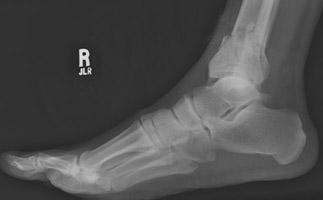

- Click on the image for a larger versionCLateral radiograph of the foot. This also demonstrates the fractures of the distal fibula and tibia.